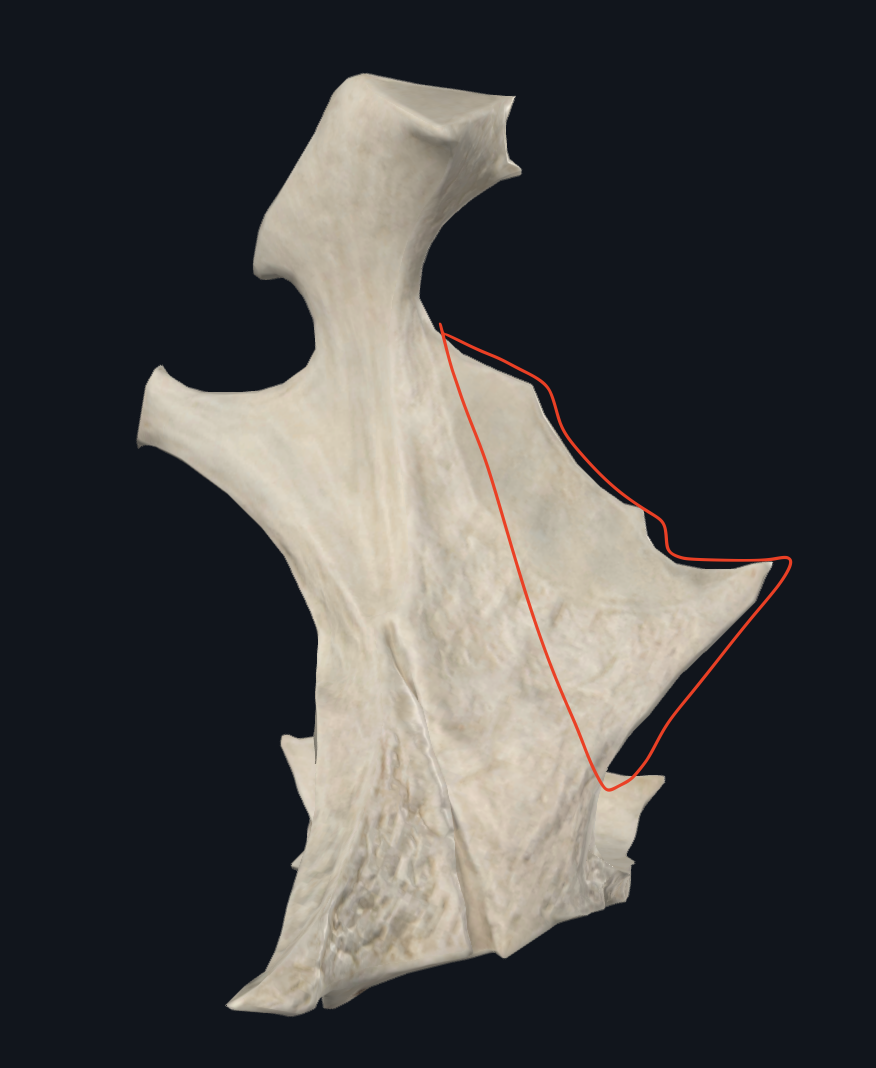

Lámina vertical del palatino

Lámina horizontal del palatino

Apófisis maxilar

Cara externa articula con maxilar.

(aqui es cara externa)

Tuberosidad maxilar

pared anterior de la hendidura pterigomaxilopalatina

(Todo lo que se encuentra posterior a la apófisis cigomática)

Apófisis pterigoides

pared posterior de la hendidura pterigomaxilopalatina

Zona desnuda del palatino

segmento medio, lisa, no articular de la cara externa de la lámina vertical del palatino

Zona no articular de la lámina vertical del palatino

Segmento medio de la lámina vertical del palatino

Pared interna de la hendidura pterigomaxilopalatina

Pared externa de la hendidura pterigomaxilopalatina

Virtual, se comunica hacia la fosa intratemporal.

(Es una pared)